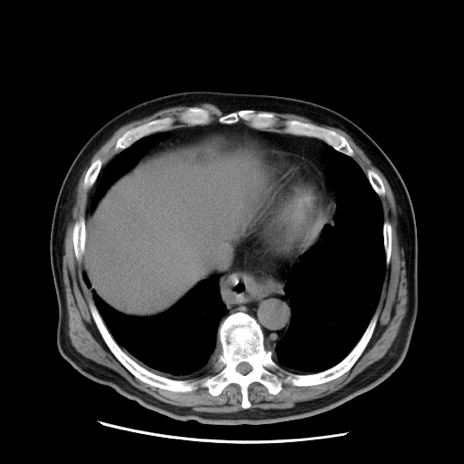

症例20(横断像)

【症例】 60歳代男性

【主訴】 腹部膨満、嘔吐

【現病歴】5日前頃より倦怠感を認め食事量減少し4日前の朝嘔吐、食事摂取困難となった。 3日前近医受診し点滴施行され整腸剤などを処方された。 当日他院を受診し、腹部膨満著明、炎症反応の上昇(CRP10.8、WBC11200)あり、紹介受診となる。

【身体所見】 意識JCS1 受け答えがはっきりしないBP 111/57mHg、 P 67bpm、、BT35.2°C、SpO2 97%(RA)、 腹部:膨隆、打診で鼓音あり、全体的に圧痛有り、腸蠕動音(-)、反跳痛ははっきりせず。

【データ】WBC 11400、CRP 14.20